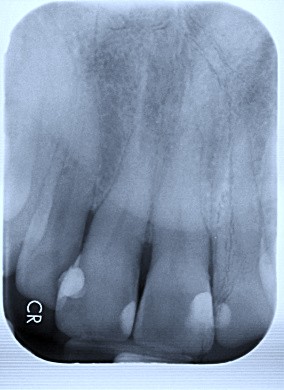

1. (Select ONE OR MORE correct answers)

The radiograph shows evidence of